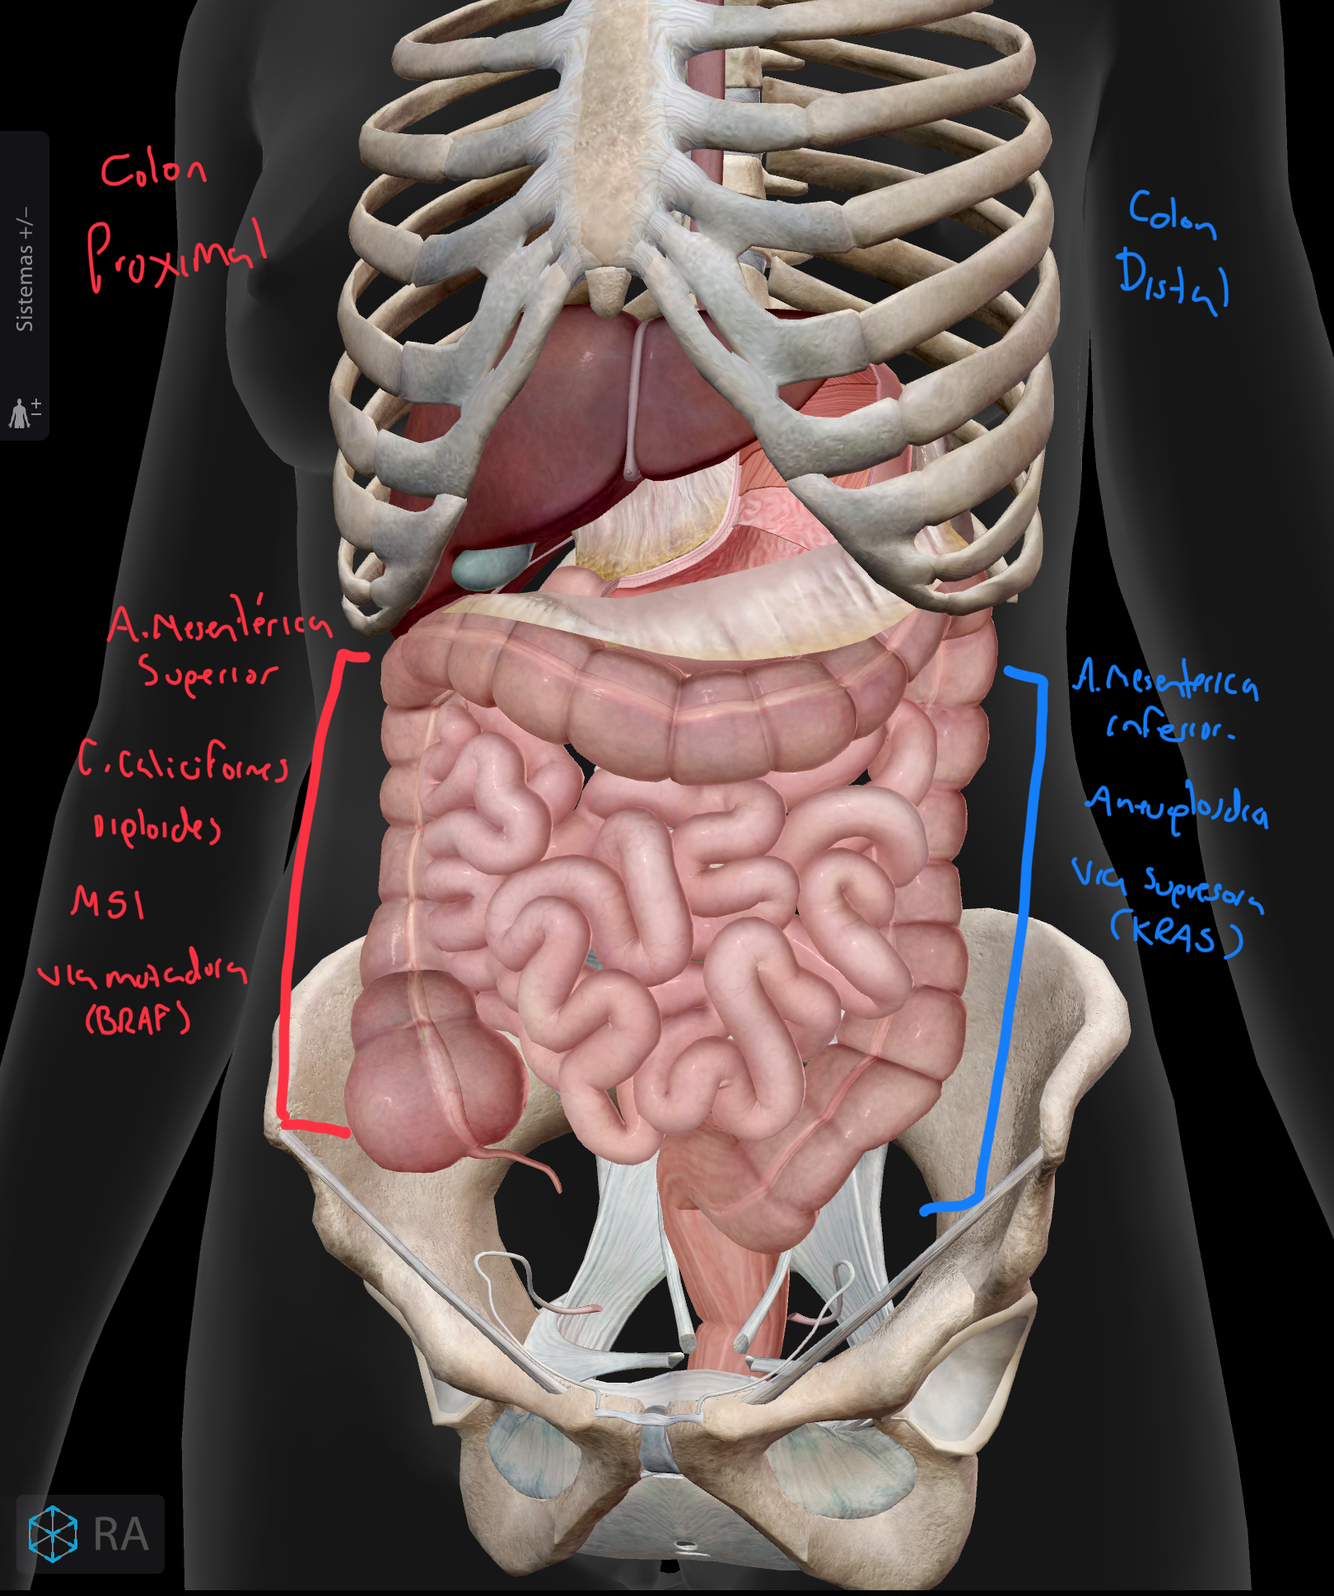

Dime si es CA proximal (derecho) o distal (izq)

1. Irrigación por a.mesenterica sup

2. Mayor número de células caliciformes y producción de moco

3. Tiene aneuplodía

4. Inestabilidad microsatelital

5. Vía supresora

6. Mutación en BRAF

A

1. Derecho, izq es por la inf

2. Derecho

3. Izquierdo, el derecho es diploidia

4. Derecho, el izq es inestabilidad cromosómica

5. Izq, el derecho es vía mutadora

6. Derecho, el izq es KRAS

Genéticamente ¿Qué mutaciones se asocian al Ca derecho e izquierda?

• Derecho: BRAF

• Izquierdo: KRAS